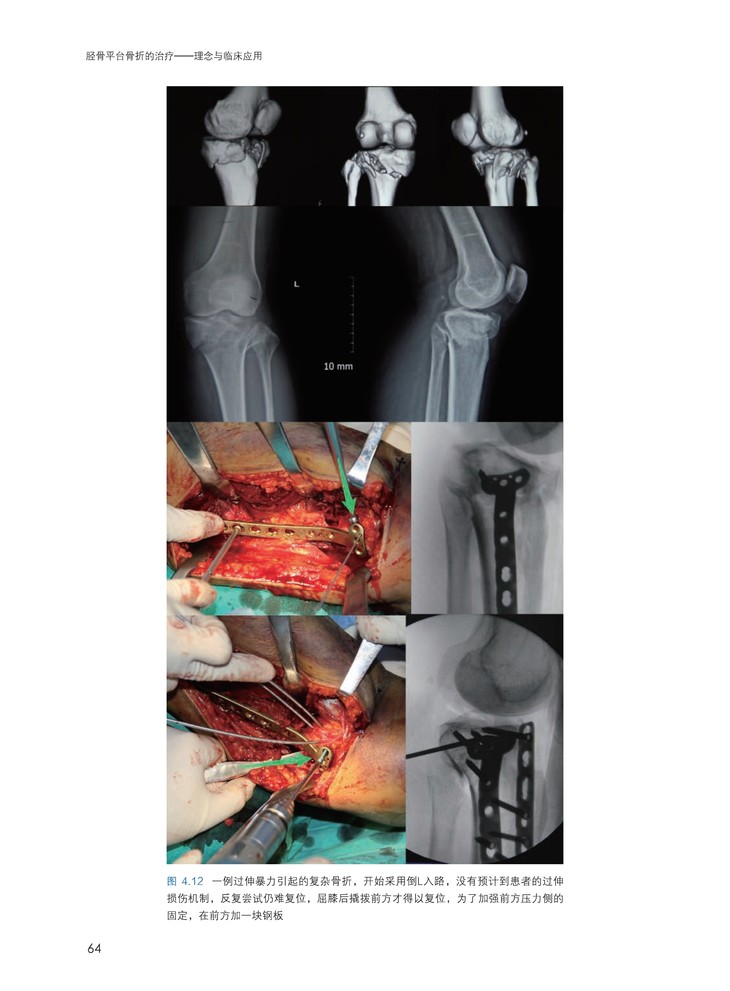

全书分为理念和临床应用两部分。理论部分详细阐述胫骨平台骨折三维形态与治疗之间的关系膝关节周围各韧带和软组织损伤的解剖、生物力学以及诊治理念和技术,手术规划,手术入路,非手术治疗,术后康复等。临床应用部分主要以病例形式体现,分为十二个专题,贴近临床实战,从急诊室的接诊到手术计划、从术中技巧到术后康复,完整地展现了骨折的实际诊治流程。大量的照片和细致的标注,充分展现了术中的技术细节和病例的诊治全程,在“关键点”处配有视频(扫码观看),带给读者真正的临场感。3D打印技术等前沿技术的应用也有详细的介绍。